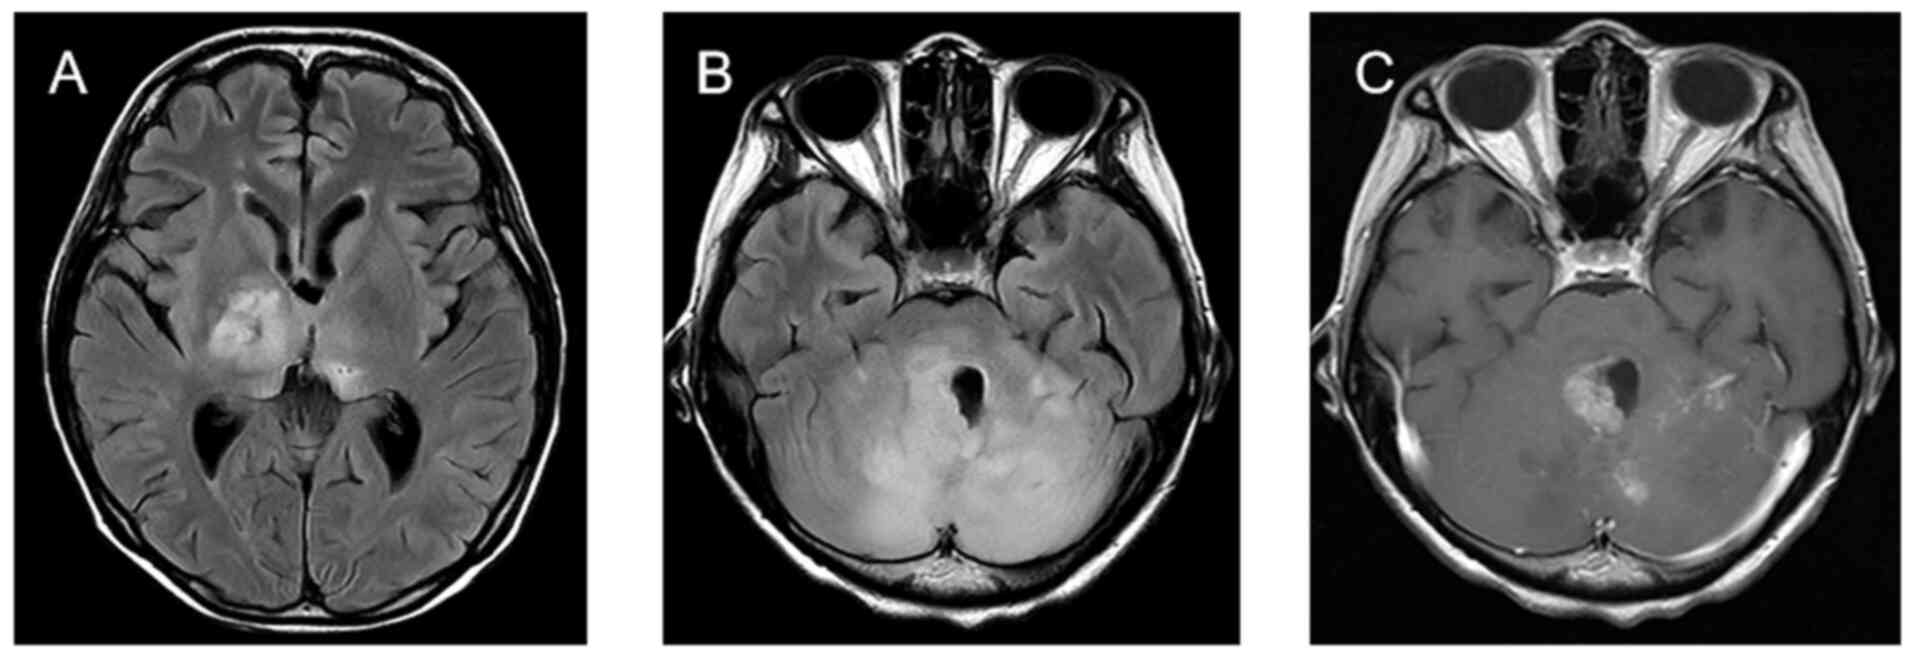

Personalized combination therapy for diffuse midline glioma: A case report

The present study aimed to analyze the efficacy of personalized combination therapy for patients with H3K27M mutant diffuse midline glioma (DMG) so as to explore new treatment options for further clinical research. The clinical data and prognosis of a patient with H3K27M mutant DMG are summarized and discussed in the context of the relevant literature. The patient was a 20‑year‑old female diagnosed with DMG treated with a combination of surgery, radiotherapy, chemotherapy, electric field therapy, immunotherapy and targeted therapy. An overall survival time of 28 months was achieved. In summary, personalized treatment strategies are expected to provide longer‑lasting survival benefits for patients with DMG.